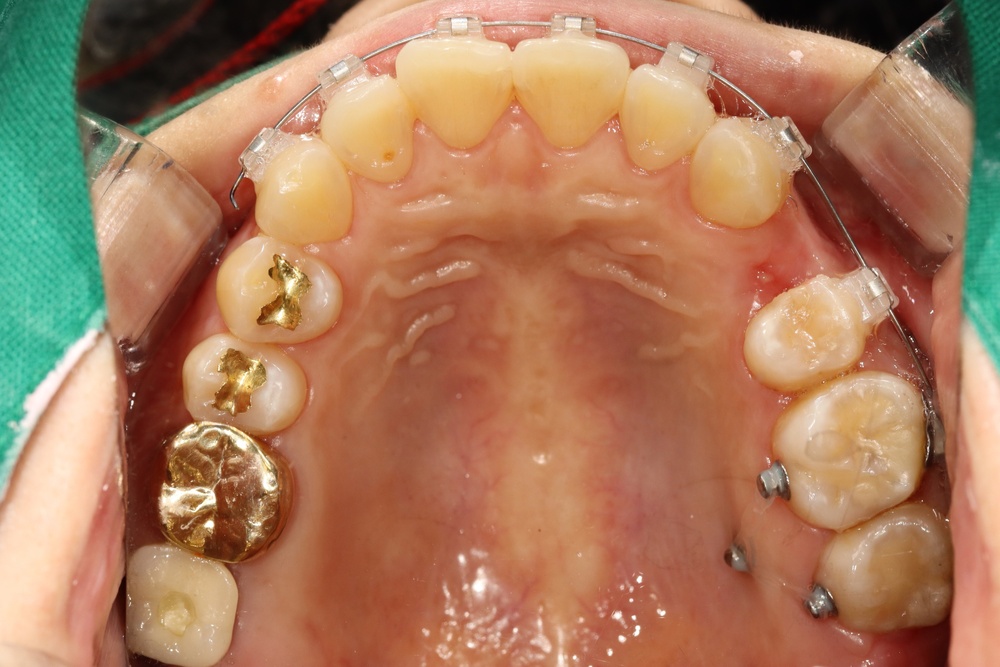

앞니가 비뚤게 나서 교정하러 온 친구입니다.

입천장의 고정식 확장장치를 이용해 좌우로 벌려서 치아를 배열할 공간을 만들었습니다.

그런데 친구가 학교에서 부딪혀서 다쳐 왔습니다.

바로 처치(치아를 철사로 부목 고정)후 신경치료를 진행하였습니다.

이후 치아배열을 마무리하여 가지런한 이를 가지게 되었습니다.